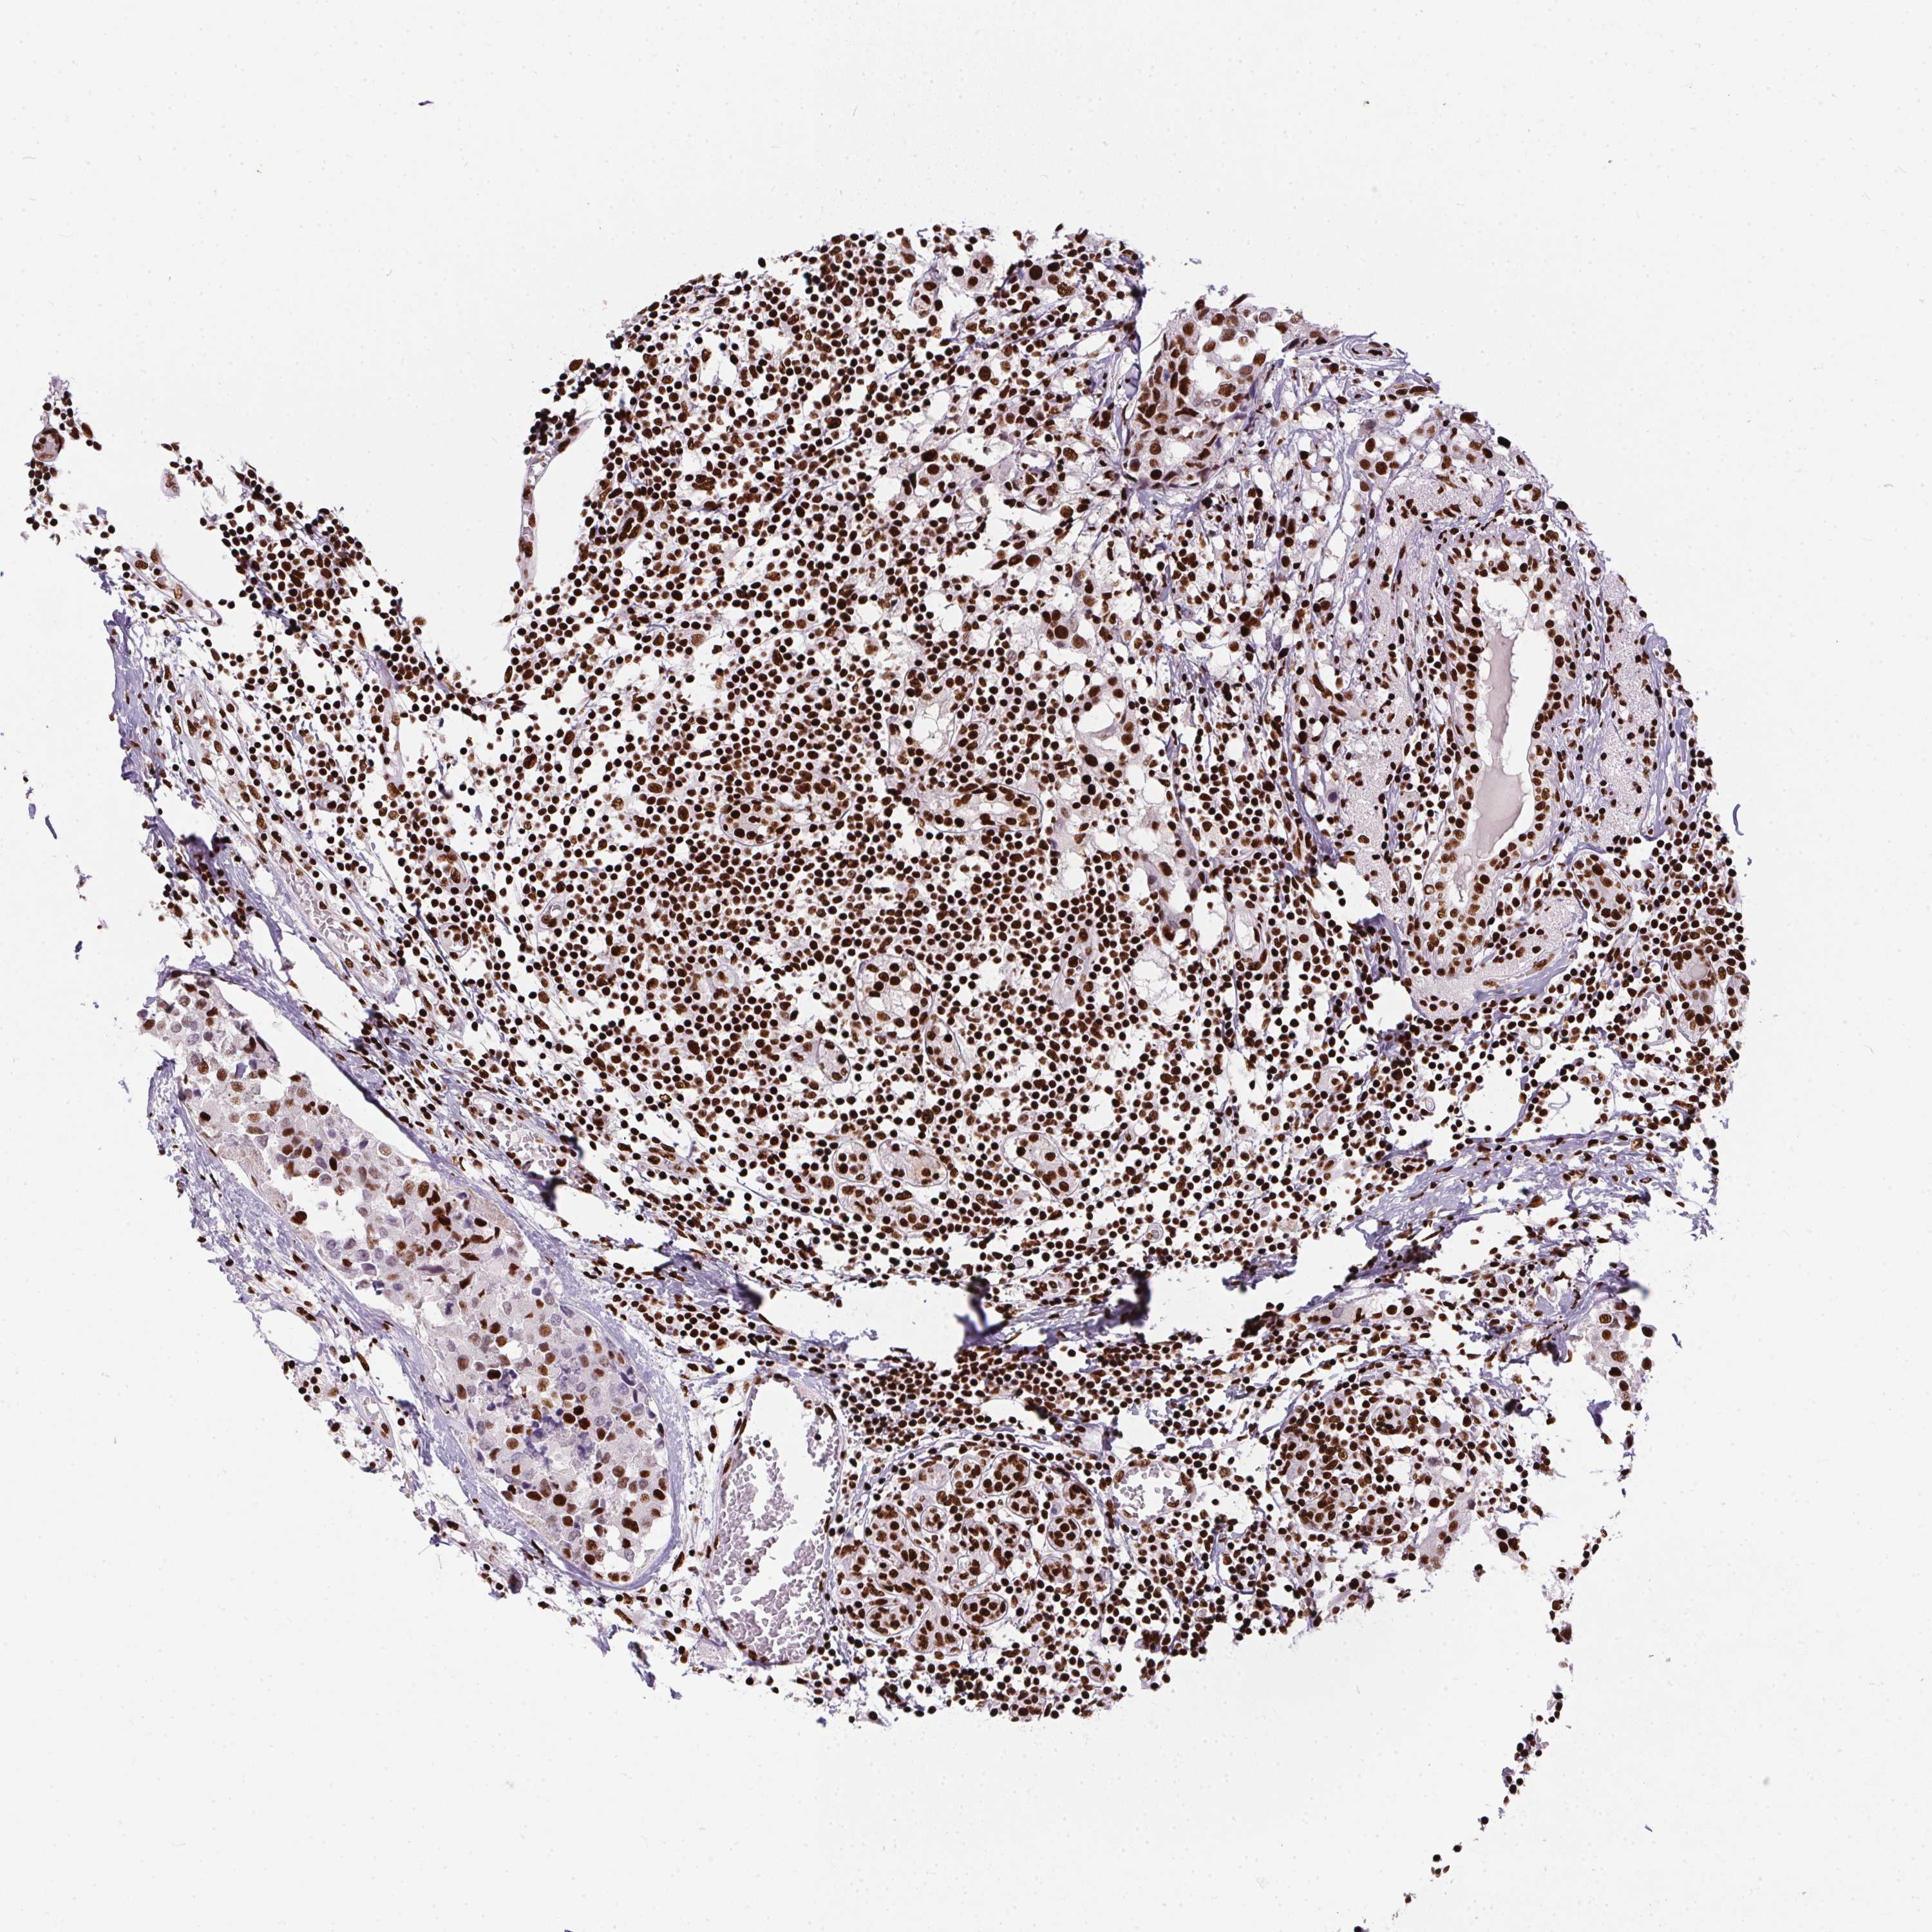

CANCER BREAST CANCER Show tissue menu

Breast cancer

Human cancer